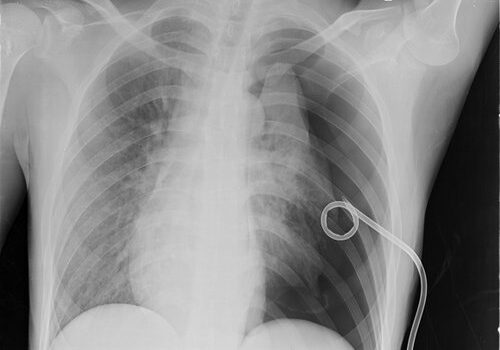

Pneumothorax: Pigtail or Chest Tube?

A patient with a hemodynamically stable spontaneous pneumothorax can be managed as an outpatient using the placement of a small-bore pigtail catheter attached to a Heimlich valve. Instruct the patient to keep the valve dry and to come in daily for chest x-rays. Once the lung is fully inflated, remove the pigtail.

Of course, that doesn’t answer the question. Which is better: a pigtail, or a chest tube connected to a Pleur-Evac container? According to the information cited by Unity Point Health, the pigtail is better. The outcomes are the same and the rates of complications are the same. However, the amount of pain the patient will experience is significantly less with a pigtail. As a bonus, there will less scarring.

- Image from Xuite Blog – Pneumothorax with Pigtail